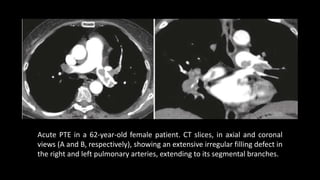

Acute PTE in a 62-year-old female patient. CT slices, in axial and coronal

views (A and B, respectively), showing an extensive irregular filling defect in

the right and left pulmonary arteries, extending to its segmental branches.